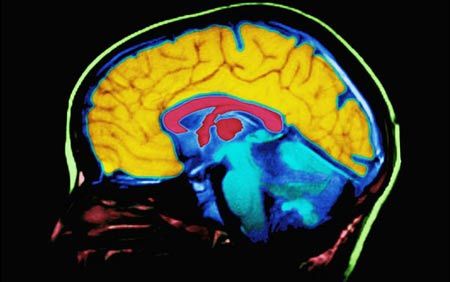

Working memory capacity is also associated with general measures of intelligence, such as reading comprehension and IQ scores, and also offers a window into the widespread, but not well understood, realm of internally driven thoughts。